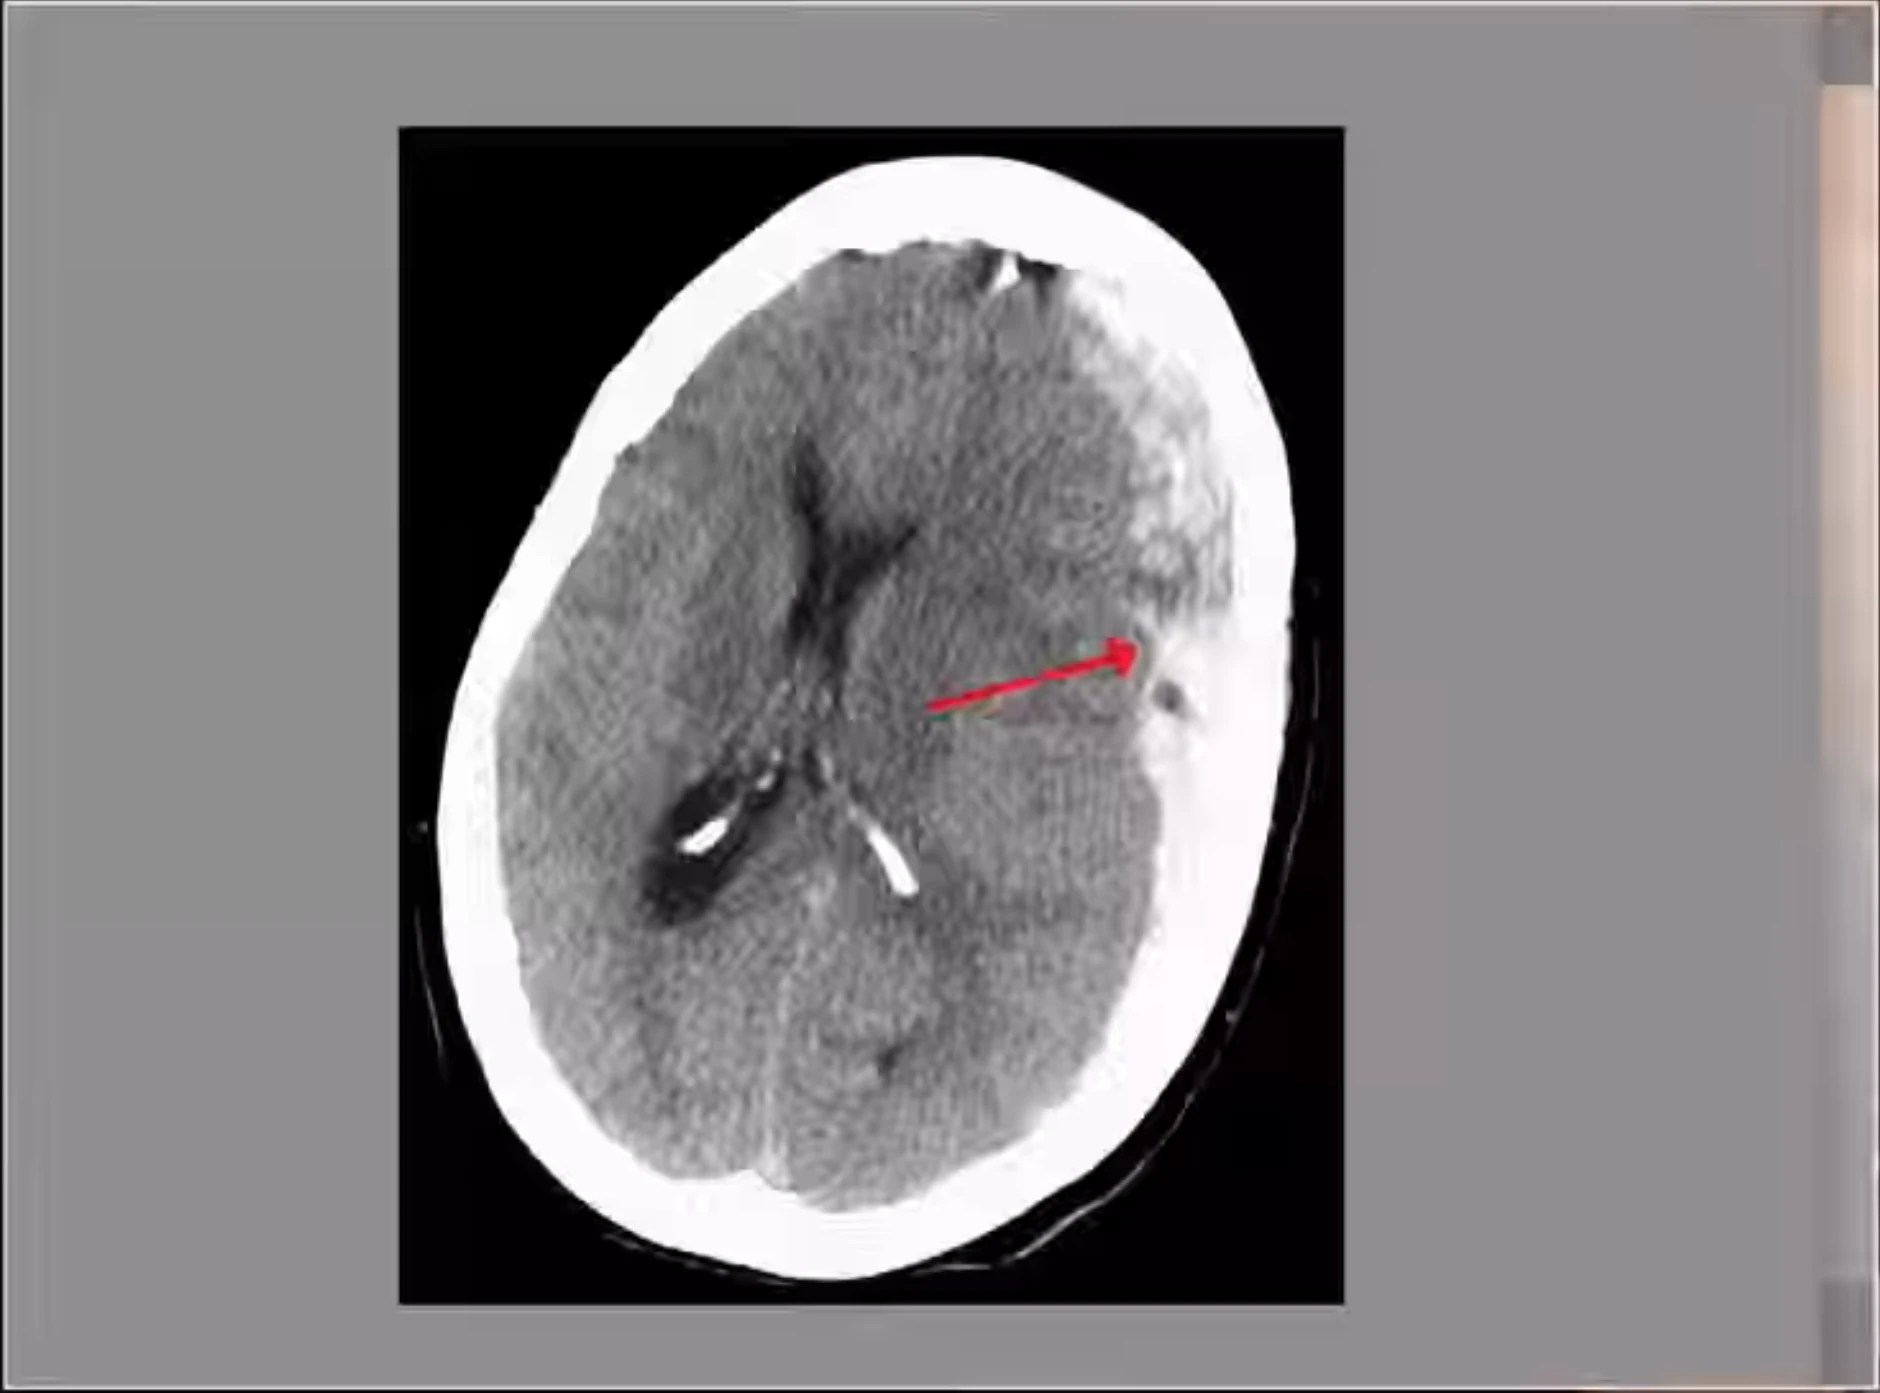

Shigetoshi Kotari and Hiromasa Urakawa have died after boxers fight due to brain injuries caused by hits during a fight which eventually lead to internal bleeding and generating a pressure on brain by a accumulated blood between skull and tissue's, above brain tissue's. Shigetoshi Kotari has died on Friday - 08.08.2025 and Hiromasa Urakawa has died on Saturday 09.08.2025. Kotari has died after fight with Yamato Hata. Urakawa has died after fight with Yoji Saito.

Video attached is a medical analysis of death causes both boxers.